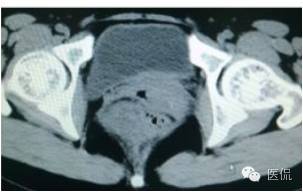

增强延迟期(CT值106HU)

手术是:盆腔占位,病理为:血管肌纤维母细胞瘤。与肛门粘连,于是同时做了肛门的处理。